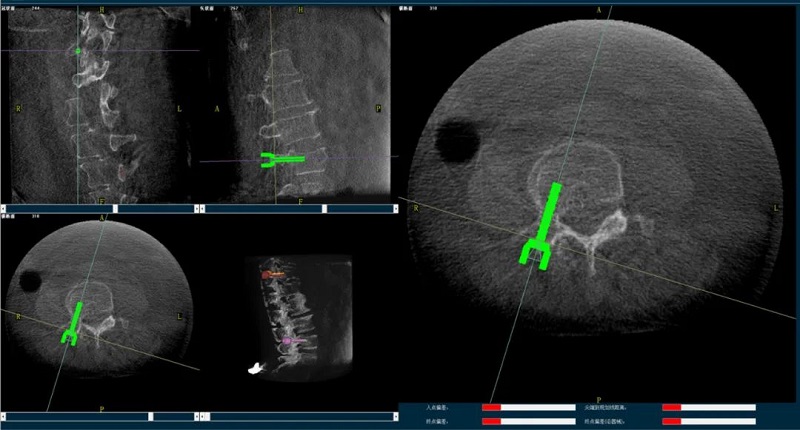

骨科手術(shù)機(jī)器人輔助下椎體成形術(shù),是以手術(shù)機(jī)器人智能機(jī)械臂為基礎(chǔ),仿照經(jīng)皮骨水泥椎體成形術(shù)的施術(shù)步驟,限定穿刺點(diǎn)、穿刺方向、角度和深度,使穿刺針經(jīng)過安全路徑進(jìn)入目標(biāo)區(qū)域,然后進(jìn)行骨水泥注入,輔助手術(shù)設(shè)計(jì)、精準(zhǔn)指導(dǎo)手術(shù)實(shí)施。以普愛醫(yī)療的骨科手術(shù)機(jī)器人為例,其輔助進(jìn)行的一例胸腰椎壓縮性骨折經(jīng)皮椎體成形術(shù)的過程如下:

(1)首先使用普愛醫(yī)療三維C形臂采集胸腰椎病灶三維圖像,對(duì)傷椎進(jìn)行三維重建;

(2)醫(yī)生制定個(gè)性化的手術(shù)方案,在機(jī)器人導(dǎo)航界面上進(jìn)行路徑規(guī)劃;

(3)根據(jù)設(shè)定好的的位置和入針方向,植入引導(dǎo)針;